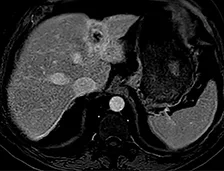

Imagerie de surveillance (figure 3)

La nécrose tumorale est visible lorsque la dose d’irradiation est élevée avec une destruction de la vascularisation tumorale. Mais la distribution inhomogène du traitement dans des lésions de grand volume rend l’interprétation radiologique difficile.

Tout d’abord une augmentation paradoxale de la taille de la tumeur peut être observée dans la phase initiale en raison de la nécrose et de l’œdème, elle est observée jusqu’à 36 % des lésions durant le 1er mois. Par conséquent, l’évaluation de la réponse tumorale doit être effectuée après 3 mois (98). La décroissance en taille de la lésion est très lente, avec une réponse complète et des critères d’amélioration qui augmentent avec le temps : dans l’étude de Lee et al., la réduction de la taille de la tumeur est de 2 % à 1 mois, 14 % à 3 mois, et 28 % à 6 mois (99). Bien que la diminution de la taille de la tumeur soit rassurante, l’absence d’augmentation dans le temps est un signe positif, et peut être considéré comme le reflet d’une réponse clinique, car l’histoire naturelle de la tumeur est la poursuite de la croissance tumorale…

Il est préférable d’utiliser les critères mRecist pour juger de l’efficacité du traitement (100), mais les variations du réhaussement tumoral, la diminution de l’hypervascularisation peuvent se faire attendre. Les données de Lee et al. montrent une amélioration selon mRecist dans 31 % des cas à 1 mois, 50 % à 3 mois et 59 % à 6 mois. Par conséquent, il faut attendre jusqu’à 3-6 mois avant de prendre la décision de retraiter, le meilleur signe de progression étant l’apparition de nouvelles lésions péritumorales ou à distance dans le foie.

| Acquisition en IRM à la phase artérielle et portale de l’injection d’un carcinome hépa- to-cellulaire de 8 cm de diamètre sur hépatopathie dysmétabolique chez un patient de 63 ans présentant une contre-indication formelle à la chirurgie en raison d’une myocardiopathie ischémique avec dysfonction ventriculaire contre-indiquant une prise en charge chirurgicale. | |